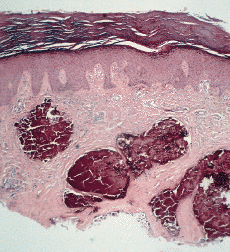

Algunas enfermedades del tejido conectivo pueden asociarse a calcificación distrófica, especialmente la esclerodermia y la dermatomiositis (26, 27). En la primera, la calcificación es habitualmente de pequeña cuantía y aparece usualmente en la piel y tejido celular subcutáneo de las manos; en el síndrome CREST la calcinosis es un rasgo fundamental para su diagnóstico e inicia el acrónimo, con lesiones de aparición insidiosa localizadas principalmente en las extremidades superiores (28) y en especial en los dedos de las manos (Fig. 2), las que pueden ulcerarse y dar salida a un material grumoso calcáreo. Los depósitos de calcio se presentan como nódulos de 1 mm a 2 cm de diámetro o como microdepósitos en la dermis normal en forma de microcristales perifibrilares o cristales en forma de aguja (29). Su aspecto radiológico es característico (Fig. 3), por lo que raramente se biopsian (30) (Fig. 4).

FIG. 4.--Síndrome CREST. Depósitos de calcio en la dermis.